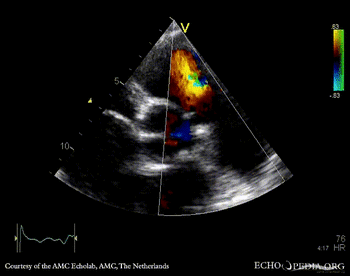

A4CH: Color Doppler, severe tricuspid regurgitation Continuous-wave signal of tricuspid regurgitation, increased systolic pulmonary artery pressure